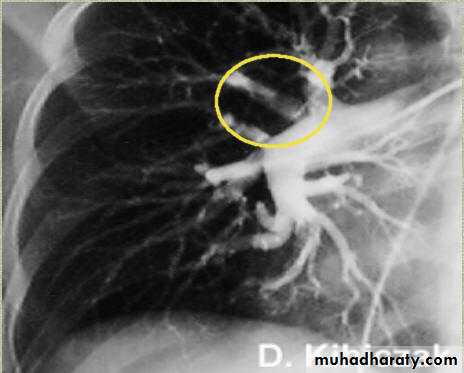

CT angio